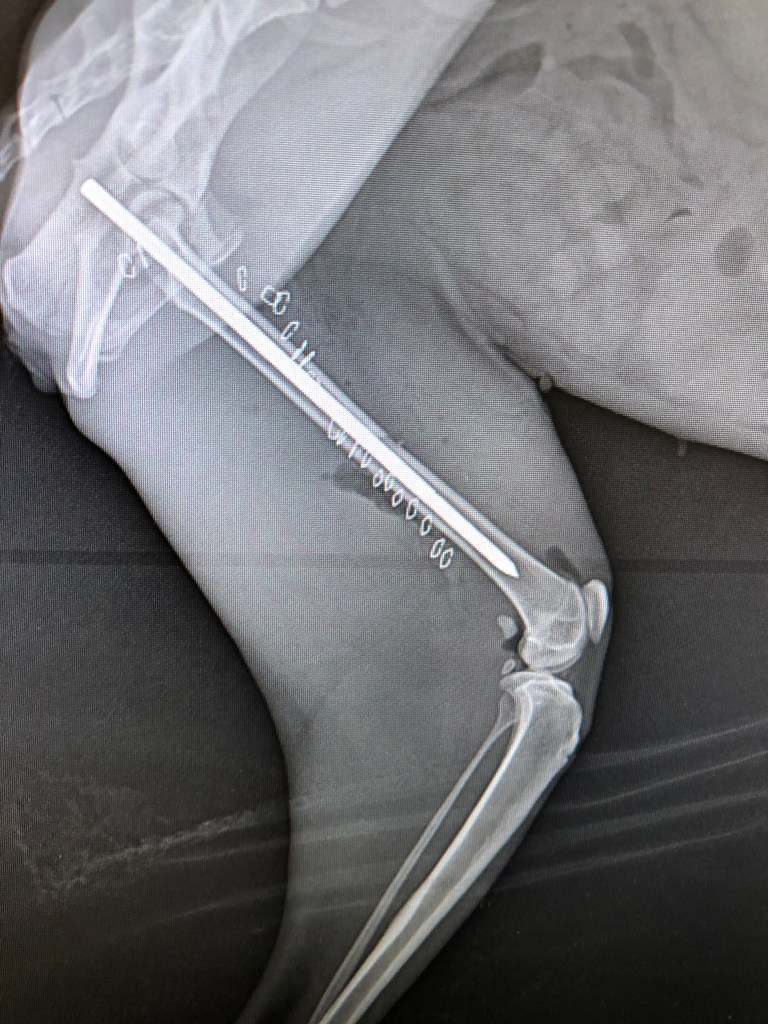

x-ray to check pin placement – looks good!

I have repaired a grand total of ONE fracture in my 18 year career (I usually send them to a specialist). so you can imagine that I was a bit stressed and fairly anxious for this procedure. As it turns out, I was able to get the bones realigned and stabilized the fragments with a pin. I can’t explain the immense relief I felt when I saw this x-ray of the pin seated just right!